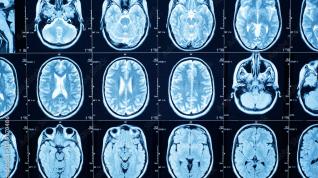

CT simulation with e-ASPECTS

Welcome to "CT-Simulation with E-Aspects", a virtual CT simulation training course designed to improve your CT interpretation skills using various CT scan examples from clinical practice in the e-ASPECTS software. This interactive training tool has been proven to increase sensitivity in identifying early signs of ischemic damage by as much as 50%.

The primary objective of this course is to support healthcare professionals in becoming skilled in CT interpretation. By using e-Aspects® software as a training tool, you will learn to implement a standardized process that will enhance your interpretive skills. You will see the results of your work instantly, allowing you to make the necessary adjustments to your method.

In the e-Aspects® training tool, you will be able to practice your skills on 80 CT scan cases:

• The first 10 cases are unprocessed cases to establish your baseline skill level.

• Next there are 60 practice scans for which you will see the solutions after submitting your result.

• After practicing with the 60 WOW scans, the system will present you with the 10 baseline cases again, albeit in a different order, to ascertain how much your skill level has improved.